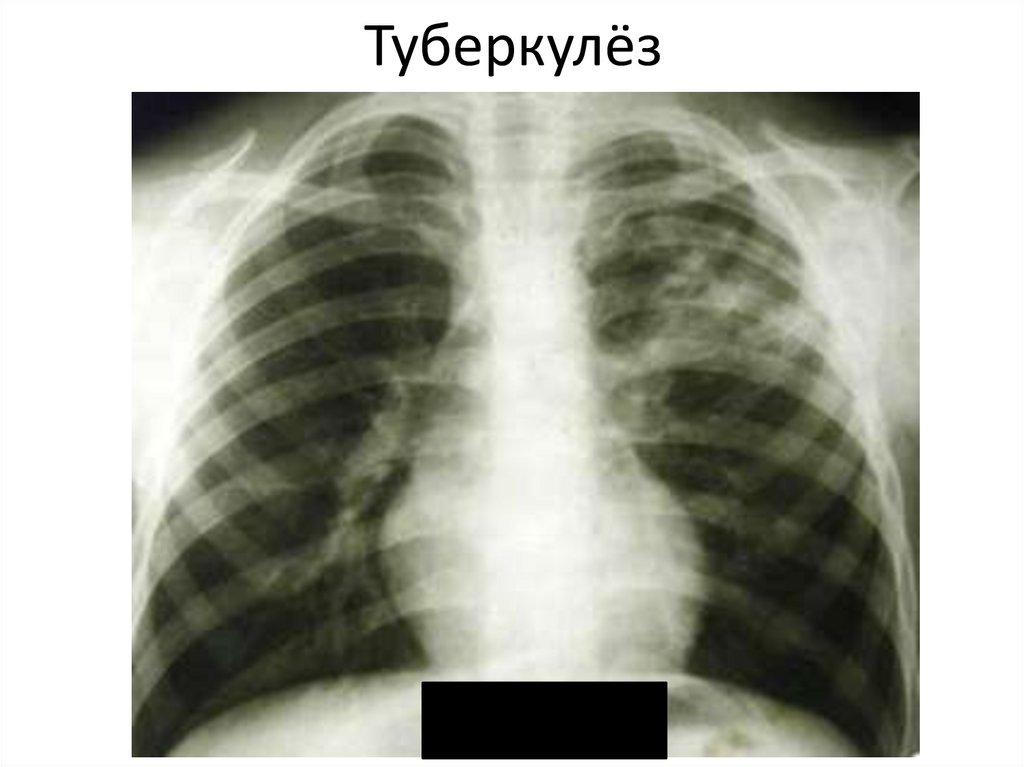

Туберкулёз